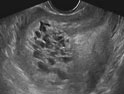

葡萄胎是指妊娠后胎盤(pán)絨毛滋養(yǎng)細(xì)胞增生,間質(zhì)高度水腫,形成大小不一的水泡,水泡間相連成串,形如葡萄,亦稱水泡狀胎塊(HM)。葡萄胎分為兩類:①完全性葡萄胎 胎盤(pán)絨毛全部受累,整個(gè)宮腔充滿水泡,彌漫性滋養(yǎng)細(xì)胞增生,無(wú)胎兒及胚胎組織可見(jiàn);②部分性葡萄胎 部分胎盤(pán)絨毛腫脹變性,局部滋養(yǎng)細(xì)胞增生,胚胎及胎兒組織可見(jiàn),但胎兒多死亡,有時(shí)可見(jiàn)較孕齡小的活胎或畸胎,極少有足月嬰誕生。